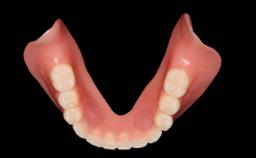

A 93-year-old female patient presented in September 2010 with an enlarged swelling on the lingual side of her lower incisors. At the time, she was essentially healthy, except for reduced vision due to bilateral age-related macular degeneration. She had been a heavy smoker (about 30 cigarettes a day) for the past 20 years after becoming a widow. The patient lived at home by herself, with full-time domestic support. An extraoral examination revealed nothing adverse. Intraoral plaque control was anything but ideal, and a soft-tissue tumescence was visible around the lingual aspect of 41–42. Because the nature of the lesion was not clear, a biopsy was carried out that revealed the inflammatory nature of the lesion. The panoramic radiograph showed six irregularly distributed mandibular implants supporting a full-arch prosthesis, with various degrees of interproximal peri-implant resorption. The periapical radiograph revealed interproximal bone resorption mesially and distally to implant 41.

Prosthesis Type FDP